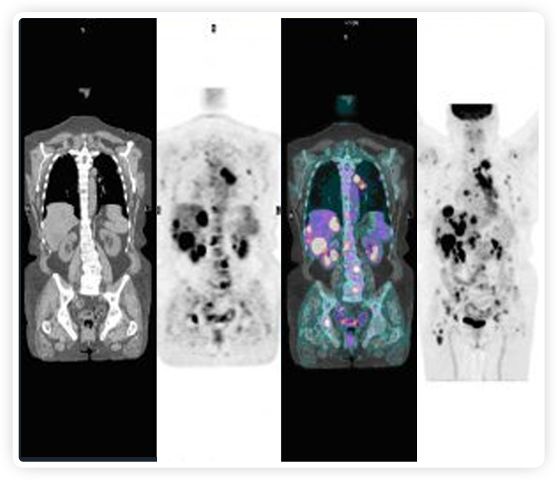

正電子發(fā)射斷層掃描(PET)是癌癥檢測中已建立的成像標(biāo)準(zhǔn),與其他成像方式相比,PET能提供高靈敏度和特異性的圖像。

到目前為止,放射腫瘤學(xué)中(使用的圖像主要是結(jié)構(gòu)性的,而PET圖像可以提供生物學(xué)信息。通過使用注射示蹤劑,例如18-FDG,PET可以描繪腫瘤的代謝活性,使其“點(diǎn)亮”。(FDG是用于可視化癌癥代謝的最廣泛使用的示蹤劑。與正常組織相比,腫瘤細(xì)胞保留更高水平的FDG。)不同的PET示蹤劑可以識(shí)別腫瘤的不同生物學(xué)特征,例如特定生物標(biāo)志物抗原(例如,PSMA)或甚至探測免疫系統(tǒng)本身(例如,PDL1表達(dá)或活化的T細(xì)胞)。